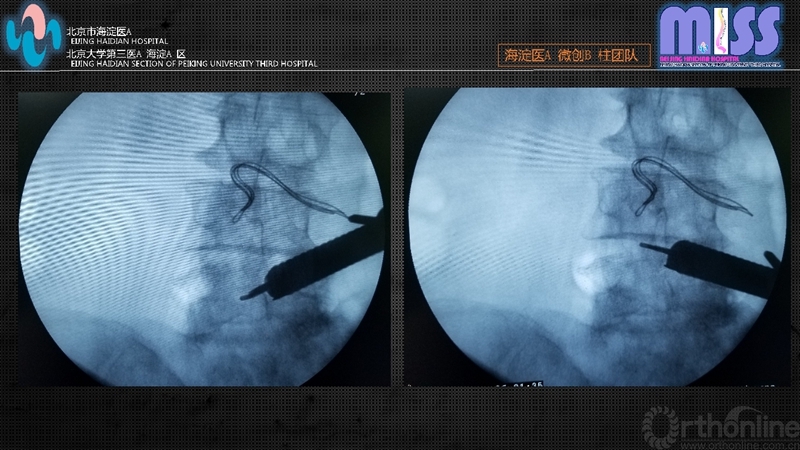

透视定位手术节段,单侧症状者由症状侧标记责任节段关节突关节内侧缘,双侧症状者全部选用右侧。透视监视下18G穿刺针穿刺至关节突关节内侧缘并适度滑下至黄韧带表面,替换为导丝后切开1cm皮肤、皮下及深筋膜,逐级软组织扩张导管扩张后拧入工作套管,斜面朝向黄韧带,透视证实位置。

置入全内窥镜并持续生理盐水冲洗,抓钳咬除通道内残留肌肉组织,双极射频止血后暴露黄韧带及部分关节突关节内侧缘。刮勺沿黄韧带表面由关节突关节内侧缘向上位椎板下缘和下位椎板上缘探查并适度刮除表面骨质将黄韧带,便于后期术中定位参考。

如椎板间隙宽度良好,可采用内窥镜下Kerrison咬骨钳依次对上位椎板下缘、下位椎板上缘及关节突关节进行部分咬除,上下咬除边界为黄韧带止点。如椎板间隙窄,先用动力磨钻磨除增生的上位椎板下缘直至咬骨钳可以操作。外侧增生的关节突关节的切除采用咬骨钳及动力磨钻交替使用,直至扩大到硬膜囊外侧。

骨性结构清理结束后咬除入路侧全部黄韧带暴露硬膜囊,将工作套管向对侧倾斜约20~30°,磨钻适度去除棘突基底部骨质,暴露对侧硬膜及侧隐窝,应用Kerrison咬骨钳咬除对侧黄韧带,磨钻处理对侧增生内聚的上关节突内侧骨质,双侧减压范围:上界为黄韧带止点,下界为椎弓根上缘,外侧边界为神经根或硬膜外缘。术中见硬膜囊膨隆无压迹,神经根无卡压。必要时可采用术中透视确定减压范围。双极射频严密止血后停止灌注,观察有无活动性出血,如无活动性出血,拔出工作套管,缝合皮肤。